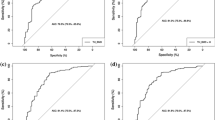

The Spearman correlation coefficient between BMD and texture parameters measured in the same ROIs ranged from −0.05 (nonsignificant (NS)) to 0.57 (p = 0.003). There was no correlation between Hmean and co-occurrence matrix nor Hmean and run length matrix in the same ROI (r = −0.04 to 0.52, NS). Co-occurrence matrix and run length matrix in the same ROI were highly correlated (r = 0.90 to 0.99, p < 0.0001). Univariate analysis with the failure load revealed significant correlation only with BMD results, not texture parameters. Multiple regression analysis showed that the best predictors of failure load were BMD, Hmean, and run length matrix at the femoral neck, as well as age and sex, with an adjusted r 2 = 0.88. Added to femoral neck BMD, Hmean and run length matrix at the femoral neck (without the effect of age and sex) improved failure load prediction (compared to femoral neck BMD alone) from adjusted r 2 = 0.67 to adjusted r 2 = 0.84.

All of the fractures were Kyle II trochanteric fractures. Mean failure load (Newton) was less for women (N = 7) compared to men (N = 5), 1,615.00 ± 554.226 and 2,816.60 ± 1,012.45, respectively (p = 0.06). Univariate analysis with the failure load revealed a significant correlation only with BMD results, not BMA ones. Results were comparable after adjustment for age and sex; r = 0.75 to 0.82 (p ≤ 0.01) for BMD and r = −0.06 to 0.54 (p = NS) for BMA parameters. Adjusted r 2 was 0.65, 0.67, 0.72, and 0.78 for the intertrochanteric region, the femoral neck, the total hip, and the greater trochanter, respectively (p < 0.0001).

Multiple regression analysis showed that the best predictors of failure load were BMD, Hmean, and run length matrix at the femoral neck, as well as age and sex, with an adjusted r 2 = 0.88. Added to femoral neck BMD, Hmean and run length matrix at the femoral neck (without the effect of age and sex) improved failure load prediction (compared to femoral neck BMD alone) from adjusted r 2 = 0.67 to adjusted r 2 = 0.84.